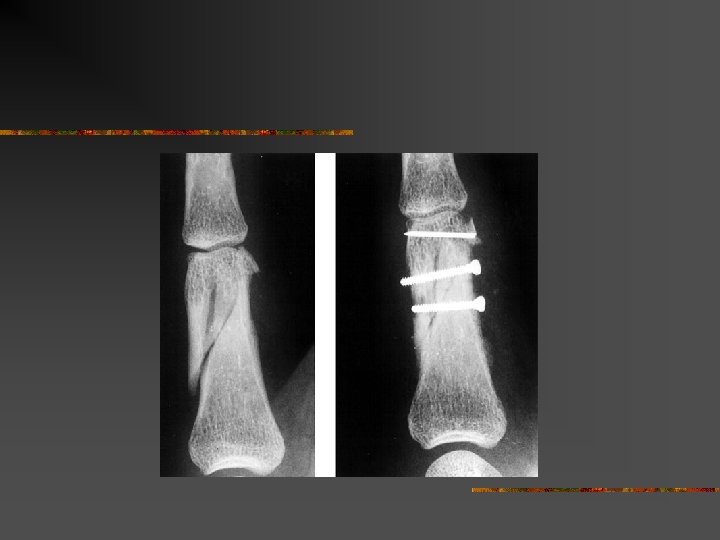

Méthode de traitement n n n Mobilisation immédiate = Tt fonctionnel Traitement orthopédique = immobilisation Traitement chirurgical = n n n Broches Vis et plaques Fixateur externe

Indications : n n Traitement chirurgical : Le but : n n Montage solide pour mobilisation précoce Eviter les raideurs

Indications : n Quelles fractures opérer ? Fractures instables ouvertes ou fermées (Fractures qui se déplacent spontanément après réduction) n Fractures articulaires n